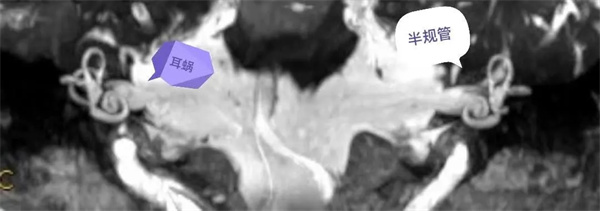

患者面肌痙攣,聽力減弱,行內(nèi)耳磁共振成像檢查。(如下圖所示)。

圖1:MIP圖,橫軸位清晰顯示雙側(cè)內(nèi)耳道,耳蝸,半規(guī)管全貌。

圖2:MIP圖,冠狀位清晰顯示雙側(cè)內(nèi)耳道,耳蝸,半規(guī)管全貌。